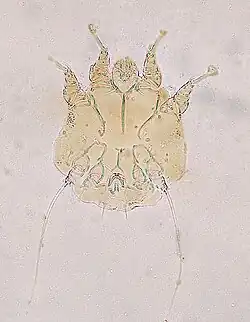

Notoedric mange, also referred to as Feline scabies, is a highly contagious skin infestation caused by an ectoparasitic and skin burrowing mite Notoedres cati (Acarina, Sarcoptidae). N. cati is primarily a parasite of felids, but it can also infest rodents, lagomorphs, and occasionally also dogs and foxes. This skin disease also has zoonotic potential.[2][3] Infestation is also called acariasis, which refers to a rash that is caused by mites.[4]

Notoedric mange is caused by the sarcoptic mite Notoedres cati that belongs to the family Sarcoptidae that consists of the burrowing mites. N. cati burrows its way through the skin of the host animal, which results in intense itching. Characteristic symptoms for Notoedric mange result from an allergic reaction of the host's body against the mites' extracellular products and also of the mechanical damage resulting from burrowing through skin.[11][12]

Most commonly N. cati as a cause of Notoedric mange may be diagnosed from a skin scraping sample with a direct microscopic identification of the mite, because there are a large number of mites present on the skin. Characteristic and systemic symptoms of Notoedric mange also help with diagnosis.[12]